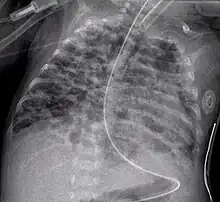

- Chest film showing increased opacity in both lungs, indicative of pneumonia